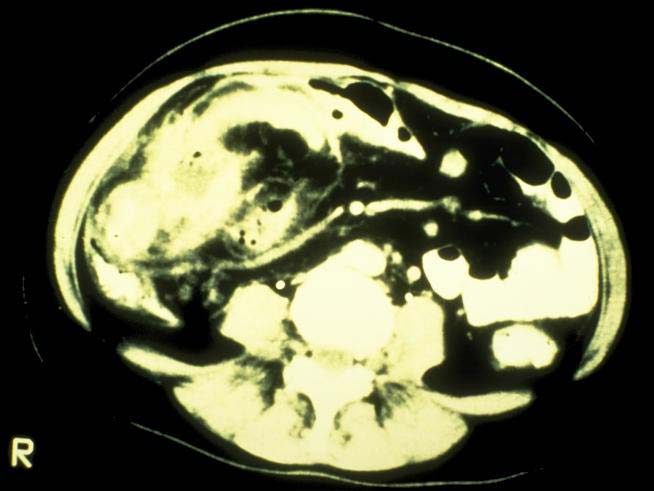

Abszesse (=Eiterhöhlen, meist im Zusammenhang mit einer Fistel),

das toxische Megacolon (=vor einer entzündlichen Verschwellung der Darmlichtung im S-Darm oder an der haarnadelförmigen linken Flexur (Dickdarm-Kurve) kommt es zu einer Stauung des Darminhaltes mit massiver Aufweitung der Darmschlinge: in schweren Fällen platzt (perforiert) der Darm und es bildet sich eine gefährliche Bauchhöhlenentzündung);(A17,A79,A19)